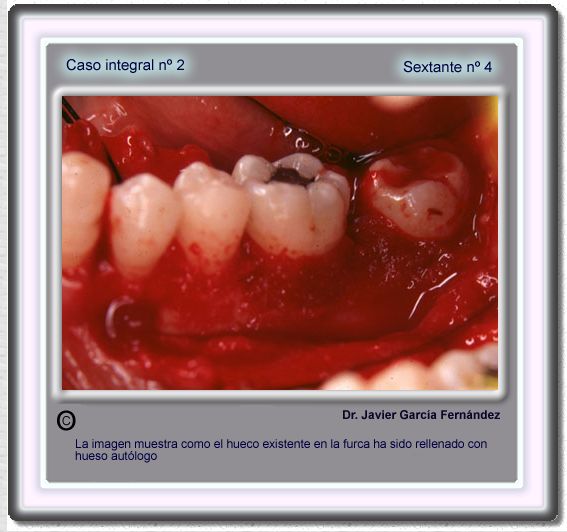

image 59